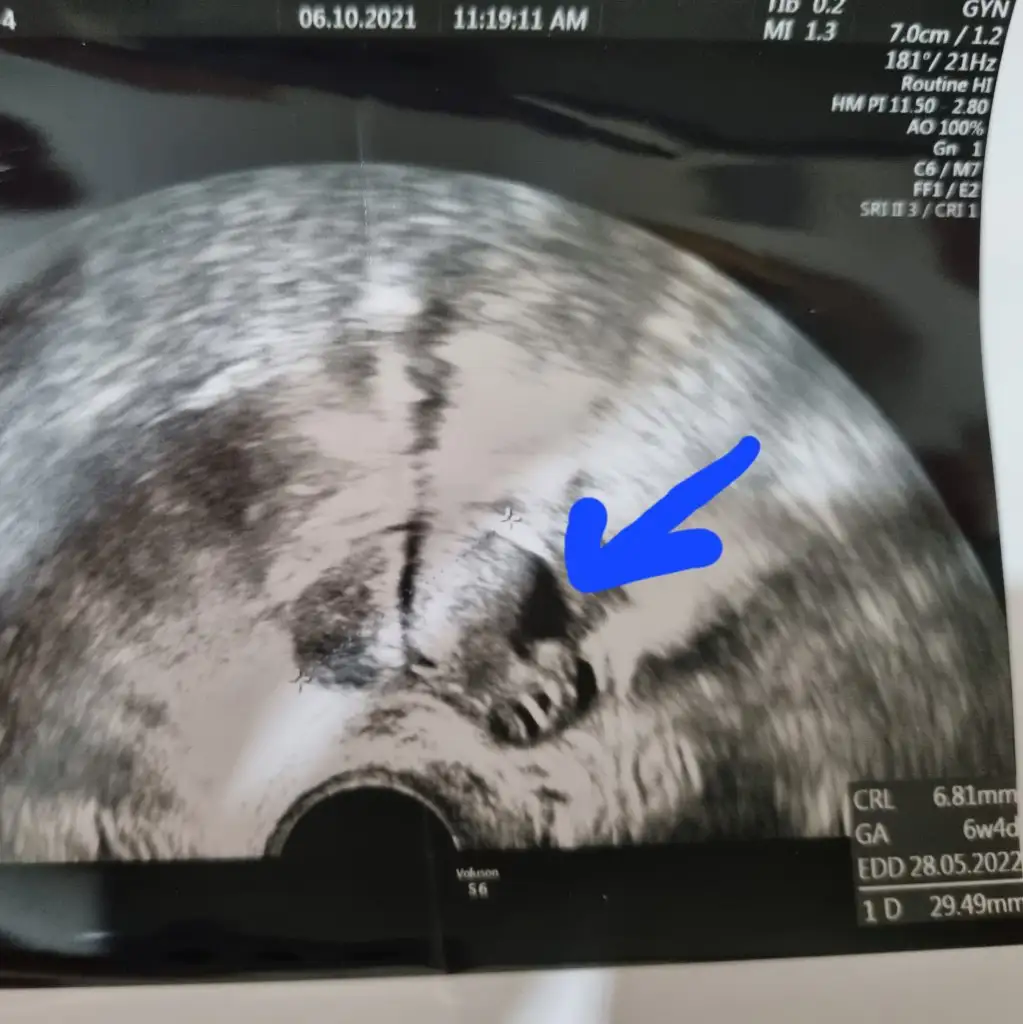

Bu da kistin görüntüsü baksana çok üzgün![]()